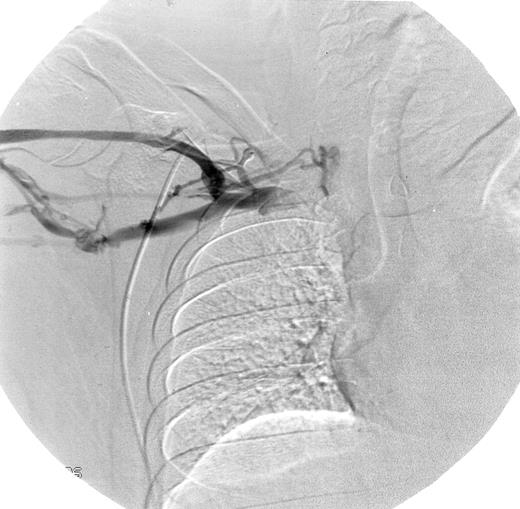

Eight of 15 patients (53%) had abnormal venograms consistent with DVT (Table 2). Five of the patients from the first study, all of whom had previously normal venograms, now had evidence of DVT. Three of the 6 newly evaluated patients also had abnormal venograms. Figure 1 shows a representative abnormal venogram (patient 14).

Abnormal venogram.

Patient 14 had multiple collateral vessels in the right mid-subclavian region providing antegrade flow around the obstruction of the proximal subclavian vein.